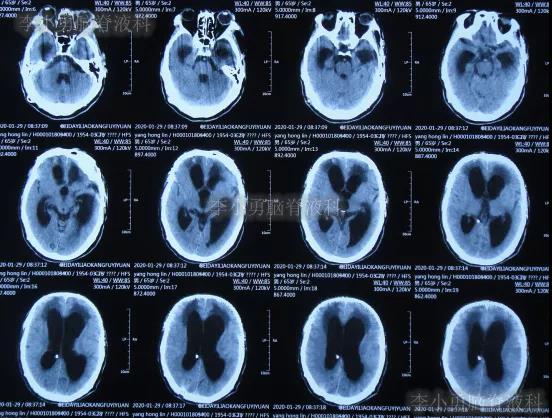

为求进一步有效治疗,于第1家医院出院后19天即2019年12月10日,住入第2家的北京某解放军的三甲医院,入院次日查头颅CT(图-14)后认为是脑积水。

图-14:2019年12月11日头颅CT

图-15:2019年12月16日头颅CT

颅骨修补术+脑室腹腔分流术后第6天即2019年12月19日,复查头颅CT示引流管周围少量出血(图-16),给予拔除头部引流,换做腰大池引流。

图-16:2019年12月19日头颅CT

腰大池引流术后5天即2019年12月24日(颅骨修补术后11天即拔除脑室引流管后5天),查头颅CT示脑室仍扩张(图-17)。

图-17:2019年12月24日头颅CT